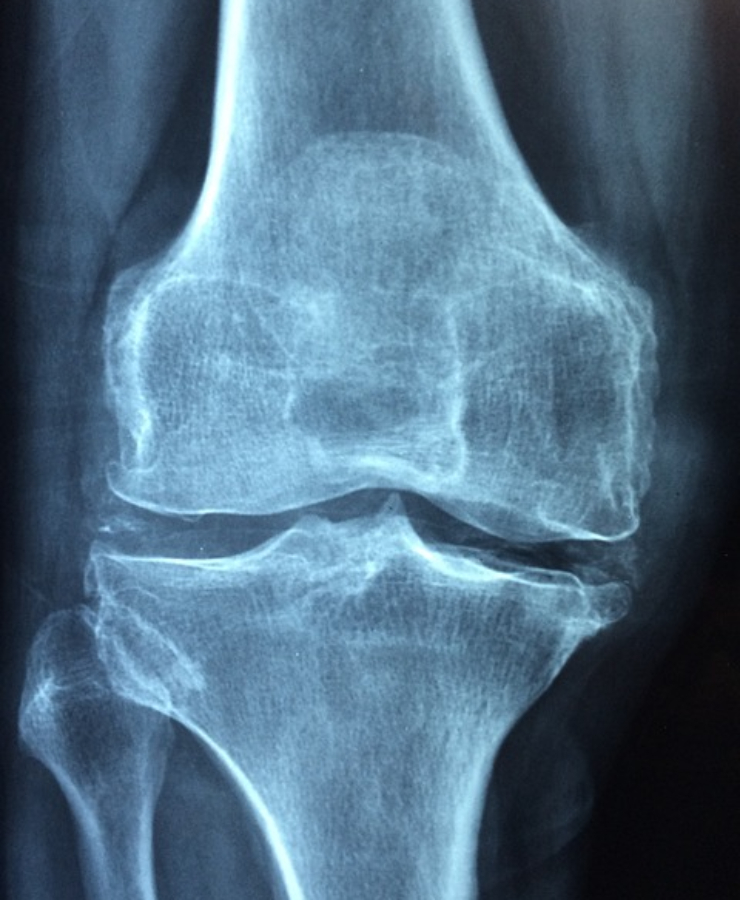

① 관절염, 관절 통증 완화

노화가 되면 연골을 이루고 있는 콜라겐이 줄어들어 연골의 수분이 감소하여 연골이 마모가 되고 결과적으로 퇴행성 관절염이 생긴다. msm은 체내의 콜라겐 생성을 도와 관절의 쿠션 역할을 하는 연골을 만들고, 관절에 염증을 유발하는 성분을 제거해 관절염과 통증을 줄여준다.

msm이 류마티스 관절염의 통증, 붓기, 뻣뻣함을 개선한다는 연구 결과들 또한 있다.